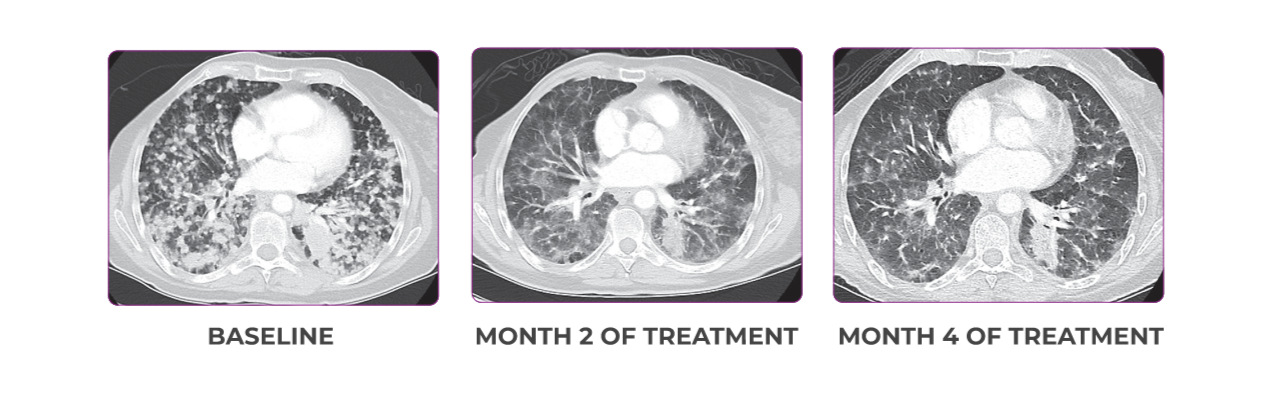

PATIENT CASE:

METASTATIC, RAIa-REFRACTORY,

PAPILLARY THYROID CANCER1

- 56-year-old female with PTCa that had metastasized to multiple sites, including the brain

- Progression after first- and second-line systemic treatment

- PRa after 4 weeks on VITRAKVI® (larotrectinib); CRa after 8 weeks

- At last assessment, complete response was sustained over an 11-month period

Response to VITRAKVI1

- After 8 weeks on VITRAKVI, all target lesions had disappeared, demonstrating a complete response

- The complete response was sustained over 11 months of treatment with VITRAKVI

- Patient experienced Grade 1 fatigue and mild hepatic enzyme elevation

Response in primary and metastatic lesions1

MRIa imagery of the lungs. Arrow indicates large target lesion in left lung.1

SCAN 1: LUNG

MRIa imagery of the brain. Arrow indicates large target lesion in left lung.1

aMRI, magnetic resonance imaging.

Images courtesy of Dr Fabian Pitoia.